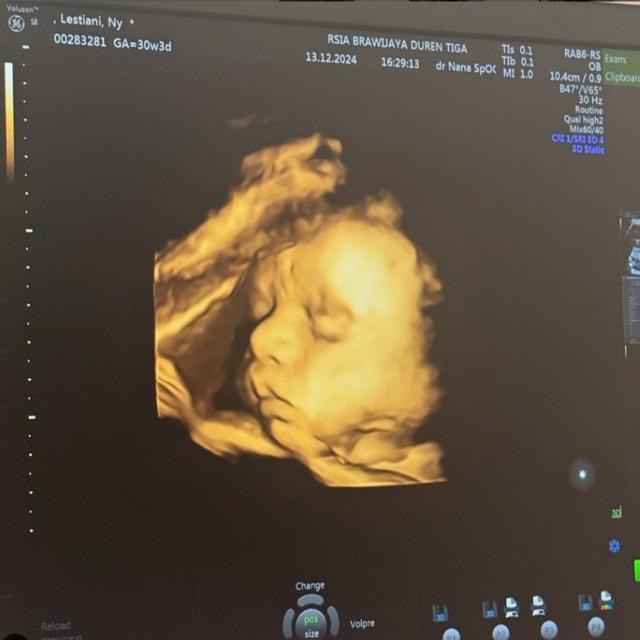

Liputan6.com, Jakarta - Rizky Billar yang sedang menantikan kelahiran anak keduanya, membagikan foto hasil USG. Dalam unggahan tersebut, wajah calon buah hati Rizky Billar dan Lesti Kejora mulai terlihat jelas seiring usia kehamilan Lesti yang kini telah memasuki trimester ketiga.

Namun, ada satu hal yang langsung menarik perhatian warganet dari foto USG tersebut, yaitu bentuk hidung calon bayi. Banyak yang menyoroti hidung sang calon bayi perempuan yang terlihat mancung dan disebut mirip dengan Billar.

"Cantik nih baby girl-nya. Hidungnya mirip papanya banget, ga bisa dikondisikan nih! Nonjok banget, duh cowok bisa lewat kalau lihat cewek ini nanti," komentar Inul Daratista.

"Masya Allah, adek sehat-sehat ya. Salfok sama hidungnya,” tulis seorang warganet.

"Masya Allah, hidungnya mancung banget,” sahut warganet lain.